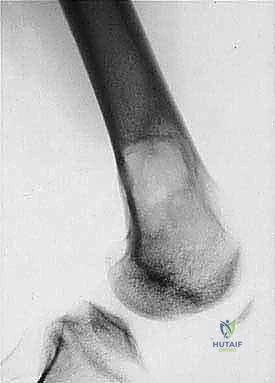

3. الكسور المرضية: حدوث كسر في العظم نتيجة إصابة طفيفة جداً لا تسبب كسراً في العظم السليم.

| حدود الورم في الأشعة | واضحة، محددة بدقة (Sclerotic margin) | غير واضحة، متآكلة (Moth-eaten appearance) |

| اختراق قشرة العظم | نادر جداً | شائع جداً، يمتد للأنسجة الرخوة المحيطة |